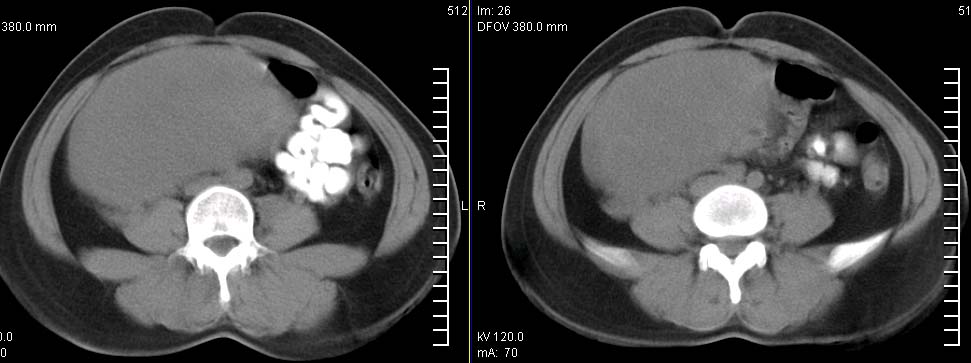

标题: CT9722:卵巢巨大占位,约10*18*21CM大小 [打印本页]

标题: CT9722:卵巢巨大占位,约10*18*21CM大小

卵巢巨大占位,约10*18*21cm大小

卵巢囊腺瘤可能性大.可见低密度

考虑:右侧卵巢囊性瘤可能性大 建议增强扫描。

肿瘤的密度有点高.和子宫差不多?且和子宫相连呢?我考虑来源于子宫,子宫巨大子宫肌瘤可能性大!(局部有坏死?)

囊腺瘤不管是浆液性,还是黏液性的,液体成分应该占的比例很大吧!!这个病灶其实是个实性肿块,更看不到囊腺瘤所能见到的分隔??请笔者提供ct值?望大家再仔细分析??

右侧附件区巨大囊性肿块,边缘光滑,密度较高,左侧缘由多个低密度区,首先考虑囊腺瘤可能。